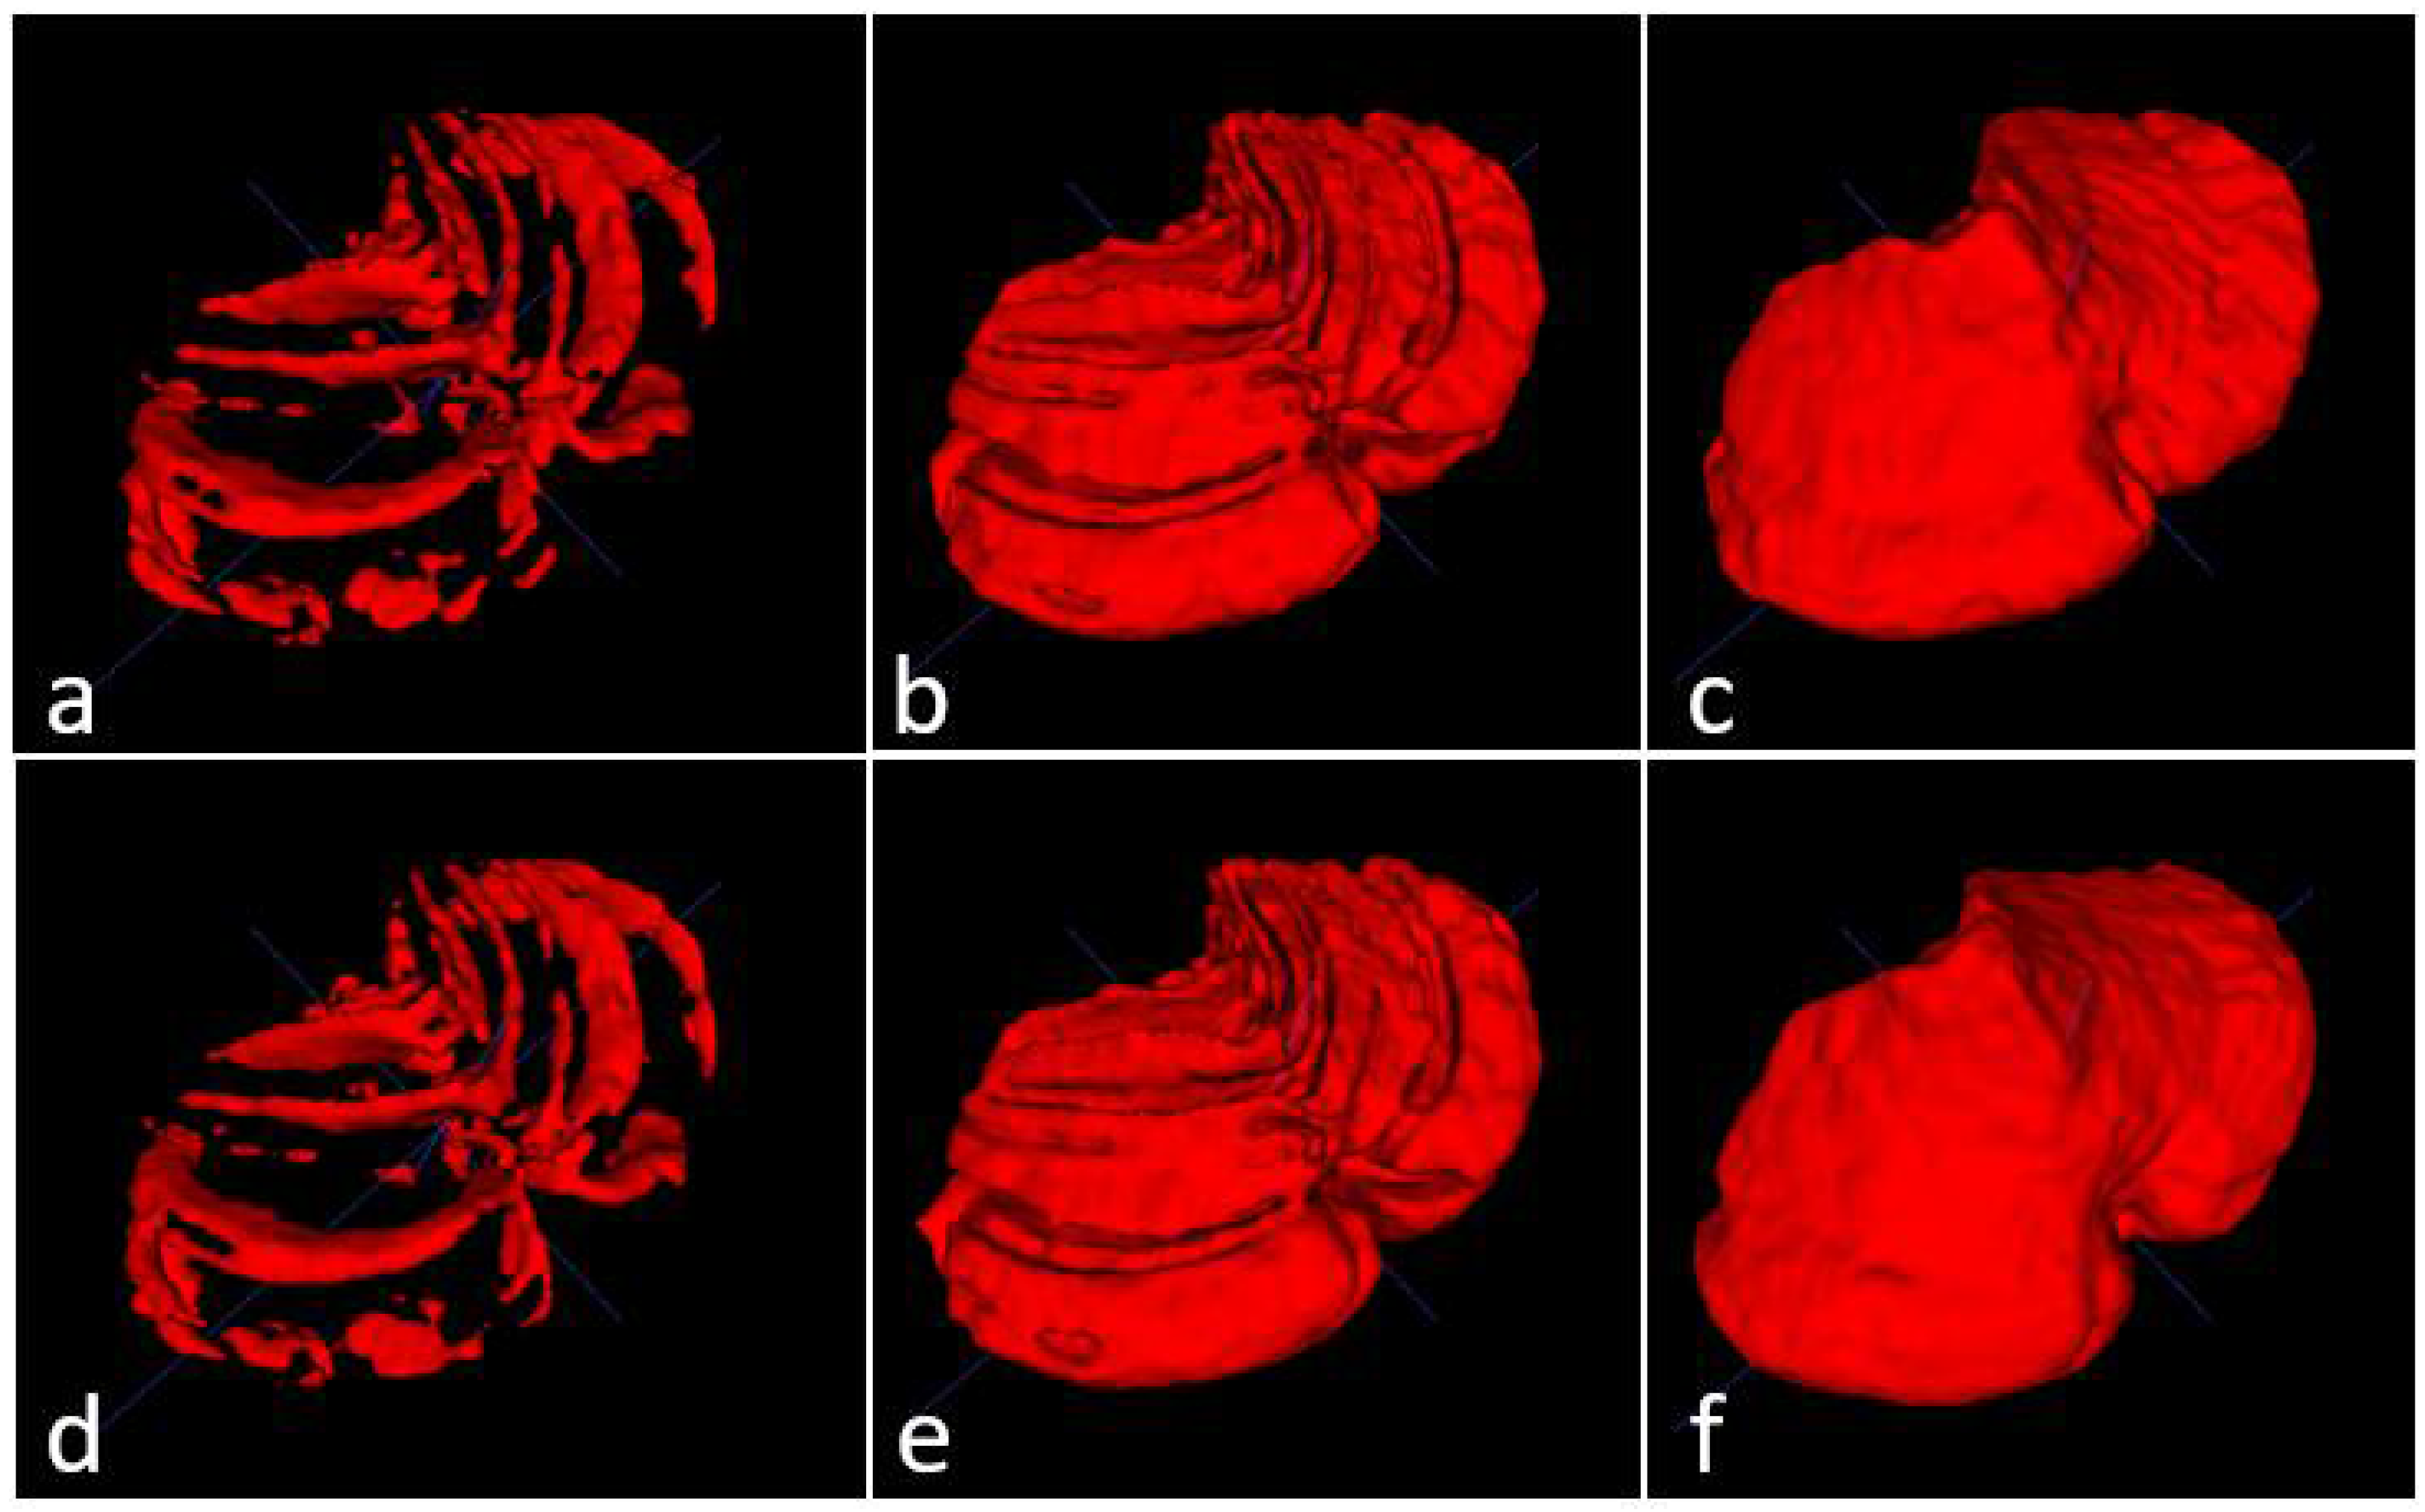

The three models (see Table 1) were tested on five unseen magnetic resonance images. The test subset contained one healthy control (subject 1), two presymptomatic carriers (subjects 2 and 4), and two SCA2 patients (subjects 3 and 5). Figure 4 shows a comparison between the original masks and the segmentations produced by M1, M2 and M3. It can be appreciated the similarity between original and segmented images. Some errors remain, mainly in the contour of segmented masks; those errors will be covered in next investigations. Table 3 shows the result of the evaluations on model M1, segmenting cerebellar fissures only.

Figure 4.

Masks and predictions for an MRI belonging to one of the SCA2 patients in the test subset. The top row shows the original masks, obtained with the procedure described in Section 2.2, and the bottom row displays the segmentations produced by our models. Cerebellar fissures in (a,d), cerebellum tissue with fissures in (b,e), and whole cerebellum without any fissure in (c,f).

Produced segmentations have relatively good scores. Mean DSC and OC are 0.854 and 0.898, respectively. All SP are above 0.99, which means an optimal recognition of background voxels. Low SN values represent some errors in the voxels belonging to cerebellar fissures, mainly in the MRI belonging to the healthy control (0.73, the minimum SN value). It seems that the best behavior was obtained for subject 3, one of the SCA2 patients in our dataset. Note that segmenting cerebellar fissures is a difficult task and, as such, characteristics change greatly between different people. Furthermore, no postprocessing was applied to the results of model M1. Figure 4d shows an example of the outputs produced by our model, compared against the ground truth mask in Figure 4a.

Table 4 shows the evaluation results for model M2 (segmentation of cerebellum tissue with its fissures). As observed, results for this model were much better than the previous one. This is a logical result, considering that segmenting a single, larger structure, which is always located in the same place on MRI, should be easier than segmenting smaller regions with many position changes. The best scores were achieved for the subject 4 MRI, producing better segmentations. The mean values for DSC and OC are 0.973 and 0.987, respectively. SP, SN and AUC are all above 0.98, which means a good background and foreground voxel classification. Figure 4e displays an example output from this model.

Table 5 shows the results for the model segmenting the whole cerebellum (M3). As in Table 4, all scores are above 0.95, which gives the idea of a high precision in the segmentation results. Mean DSC and OC are 0.969 and 0.982, respectively. As in evaluation for model M2, SP, SN and AUC are above 0.98, which means a high-quality segmentation. In a general way, the segmentations obtained by models M1, M2 and M3 have a good quality. Models M2 and M3 obtained better scores than M1.